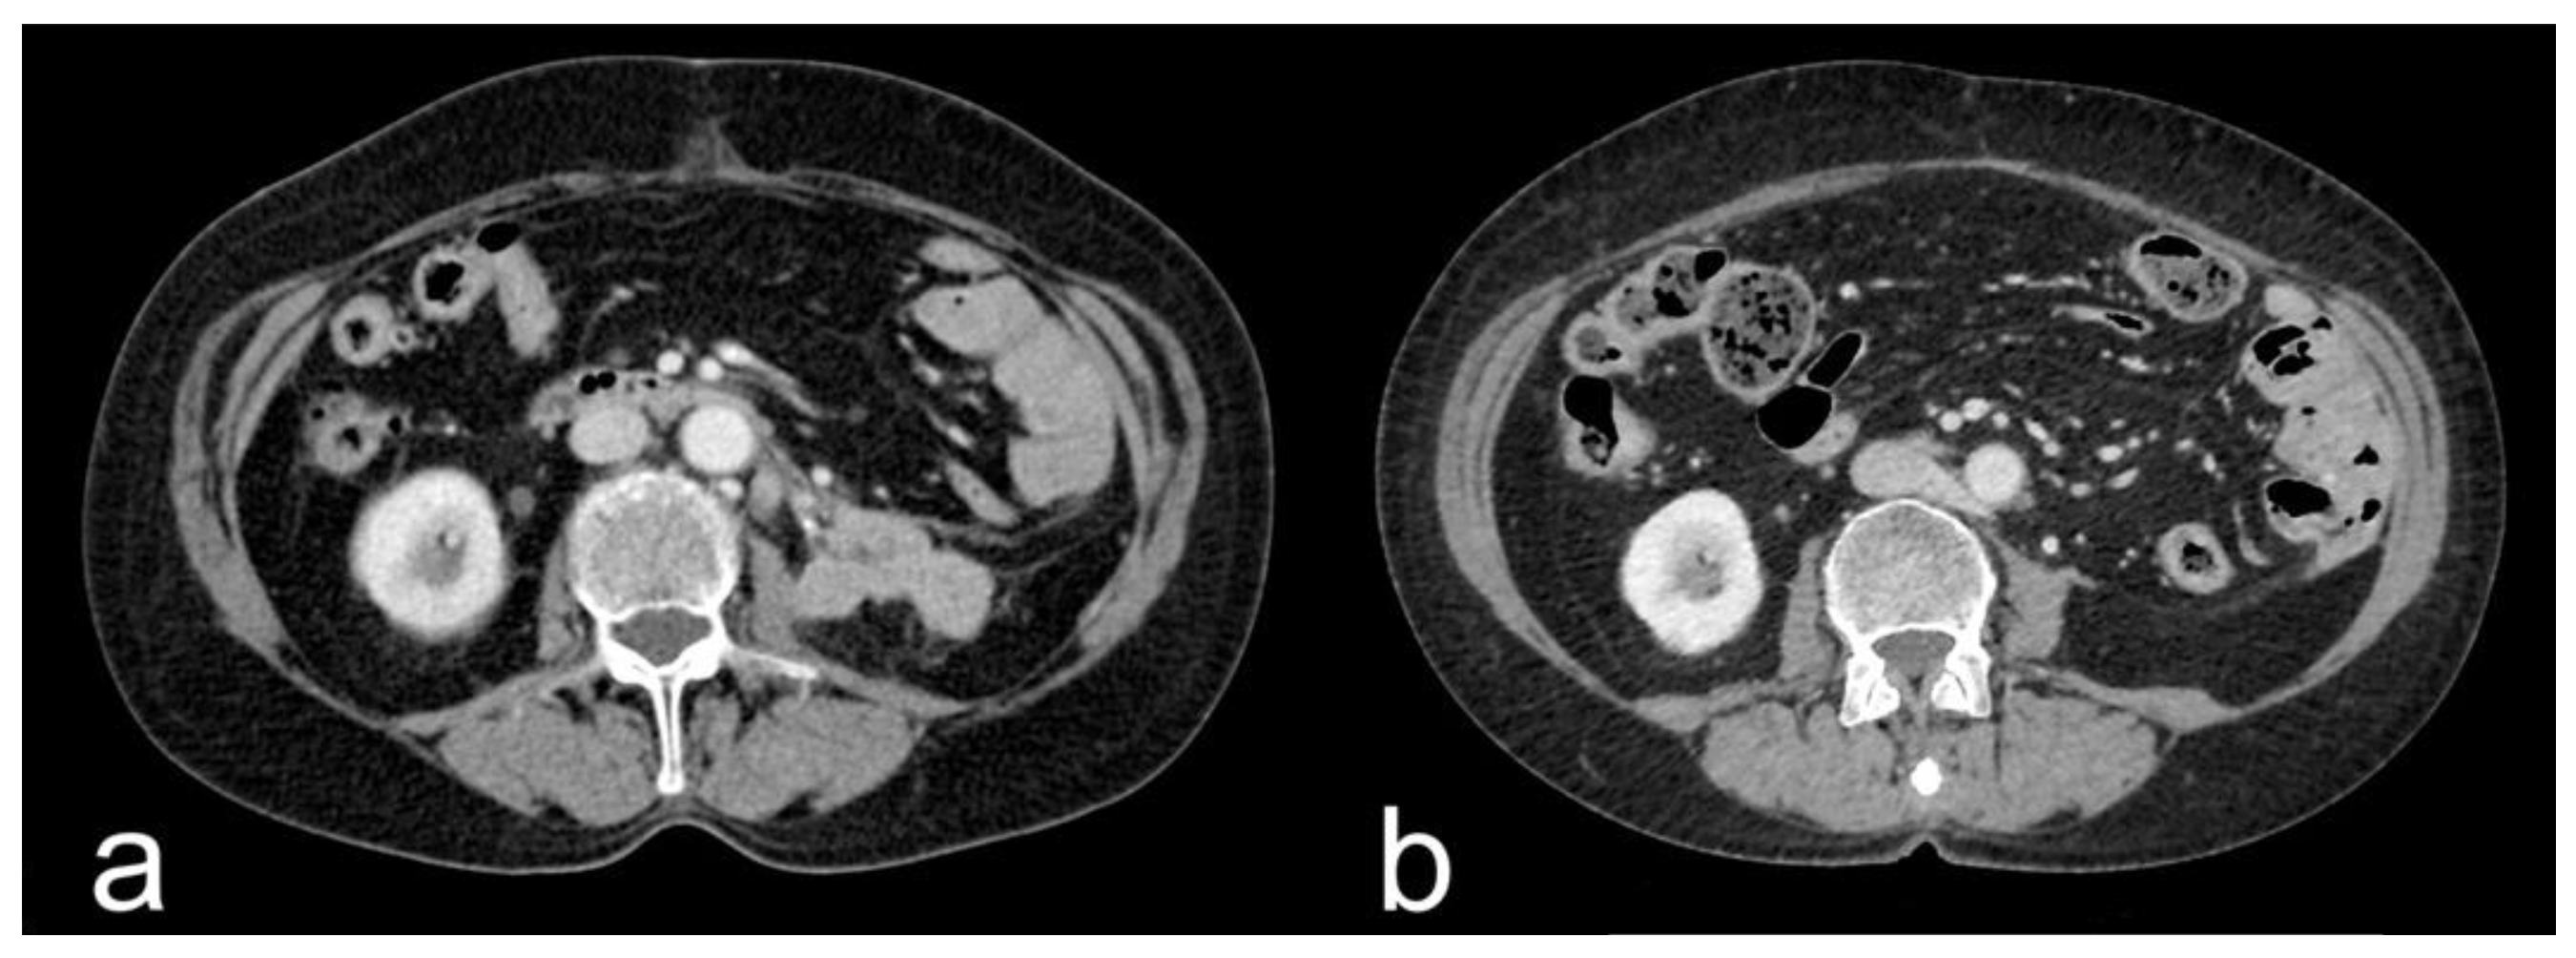

- Complete response (CR): disappearance of all target lesions together with any pathological lymph nodes (target or non-target) with short axis < 10 mm (Figure 1).